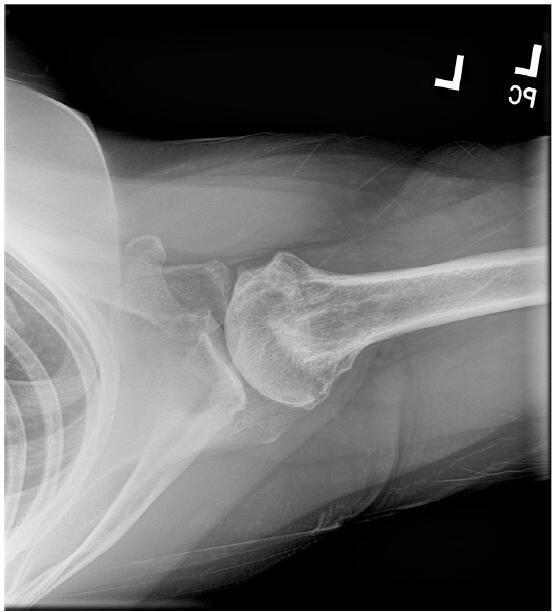

肩关节粘连性囊炎(AC)是一种常见的疾病,通常以临床病程延长和患者发病率高为特征,导致较高的社会经济负担。尽管有许多研究评估了各种治疗方式,但优化的治疗算法仍然难以捉摸。类似地,肩关节骨性关节炎(OA)表现出类似的临床和甚至更高的社会经济影响。诊断成像和短期疼痛管理方法的进步尚未产生有效的长期疾病改善疗法。随着肩关节骨性关节炎患者平均年龄的下降,人们对旨在减轻症状、提高生活质量和可能推迟侵入性手术干预的再生治疗越来越感兴趣。本文概述了AC和盂肱骨关节炎(GHOA)的病理生理学,并附有回顾性试点案例研究,证明了一种称为RELIEF®治疗的新型骨科方法的有效性。这种创新的方法产生了有希望的短期结果,包括治疗后6个月时多平面肩关节活动度(ROM)和功能评分的显著改善。RELIEF®治疗包括诊断性动态超声,以识别筋膜中的瘢痕或异常,并结合使用冷冻保存的微细化人羊膜悬浮液异体移植物(hAMA)和Isolyte晶体IV液的水解剖技术。在超声直接引导下,使用局麻药(2%利多卡因加肾上腺素1:20万)进行多次注射,目的是溶解纤维化瘢痕组织并将同种异体移植物输送到患处。治疗前和治疗后ROM评估由有执照的物理治疗师使用角度计进行。测量分别在基线(治疗前)和治疗后2周、2个月、4个月和6个月进行。此外,记录美国肩肘外科医生(American Shoulder and肘部外科医生)评分和视觉模拟量表(visual analogue scale, VAS)疼痛评分。随后在第二次RELIEF®治疗后4个月进行肩部MRI(无造影剂),以评估任何放射学上的显著变化,并将这些发现与患者报告的症状和整体功能状态的变化联系起来。

Adhesive capsulitis (AC) of the shoulder is a prevalent condition often characterized by a prolonged clinical course and significant patient morbidity, leading to a high socioeconomic burden. Despite numerous studies evaluating various treatment modalities, an optimized treatment algorithm remains elusive. Similarly, osteoarthritis (OA) of the shoulder presents a comparable clinical and an even higher socioeconomic impact. Advances in diagnostic imaging and short-term pain management options have not yielded effective long-term disease-modifying therapies. With the decreasing average age of patients suffering from glenohumeral OA, there is a growing interest in regenerative treatments aimed at alleviating symptoms, enhancing quality of life, and potentially postponing invasive surgical interventions. This paper provides an overview of the pathophysiology of both AC and glenohumeral osteoarthritis (GHOA), accompanied by a retrospective pilot case study demonstrating the efficacy of a novel orthobiologic approach known as the RELIEF® treatment. This innovative approach yielded promising short-term outcomes, including significantly improved multi-planar shoulder range of motion (ROM) and functional scores at six months post-treatment. The RELIEF® treatment involves diagnostic dynamic ultrasound to identify scarring or abnormalities in the fascia together with a hydrodissection technique using a combination of cryopreserved micronized human amniotic membrane suspension allograft (hAMA) and Isolyte crystalloid IV fluid. Under direct ultrasound guidance, local anesthetic (2% lidocaine with epinephrine 1:200,000) is utilized to perform multiple injections aimed at lysing fibrotic scar tissue and delivering the allograft to affected areas. Pre- and post-treatment assessments of ROM were conducted by a licensed physical therapist utilizing a goniometer. Measurements were taken at baseline (before treatment) and subsequently at two weeks, two months, four months, and six months post-treatment. Additionally, American Shoulder and Elbow Surgeons (ASES) scores and visual analog scale (VAS) pain ratings were recorded. An MRI of the shoulder (without contrast) was subsequently performed 4 months following the second RELIEF® treatment to evaluate for any radiographically significant changes and to correlate these findings with change in patient-reported symptoms and overall functional status.